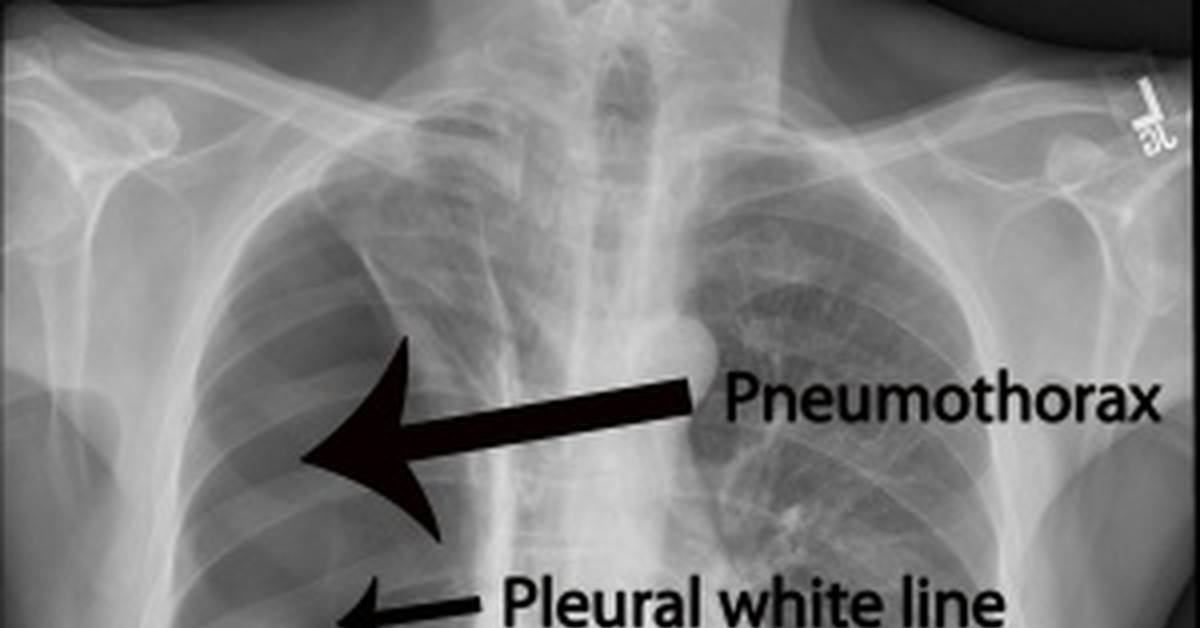

Пневмоторакс это состояние, когда плевральная полость легкого наполняется газом, который поступает туда через мельчайшие дефекты легких . Такая патология вызывает спадение пораженной . . .

Пневмоторакс на рентгенограмме: рентген-признаки плеврального воздуха Пневмоторакс на рентгенограмме проявляется просветлением с отсутствием легочного рисунка, вызванным скоплением . . .

Первичный спонтанный пневмоторакс встречается у лиц, не страдающих заболеваниями легких, как правило, у высоких худых подростков и мужчин возрасте 20-30 лет . Считают, что он вызван спонтанным разрушением . . .